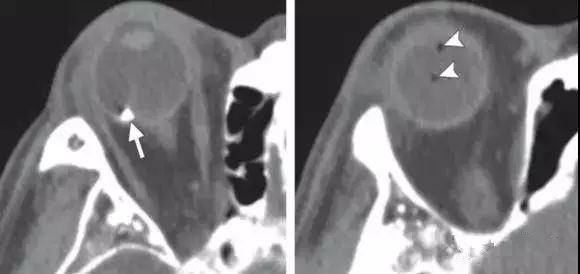

【眼球|诊断眼球外伤时,影像医生要留心的6点!】1.脉络膜小疣:视神经盘附近的通常是与黄斑变性有关

2.巩膜斑块:沿内直肌和外直肌附着点的钙化也称为巩膜斑块 , 常见于老年人 。

3.常见的用于治疗视网膜脱离的材料包括巩膜条带 , 硅油 , 以及气体 。

文章插图